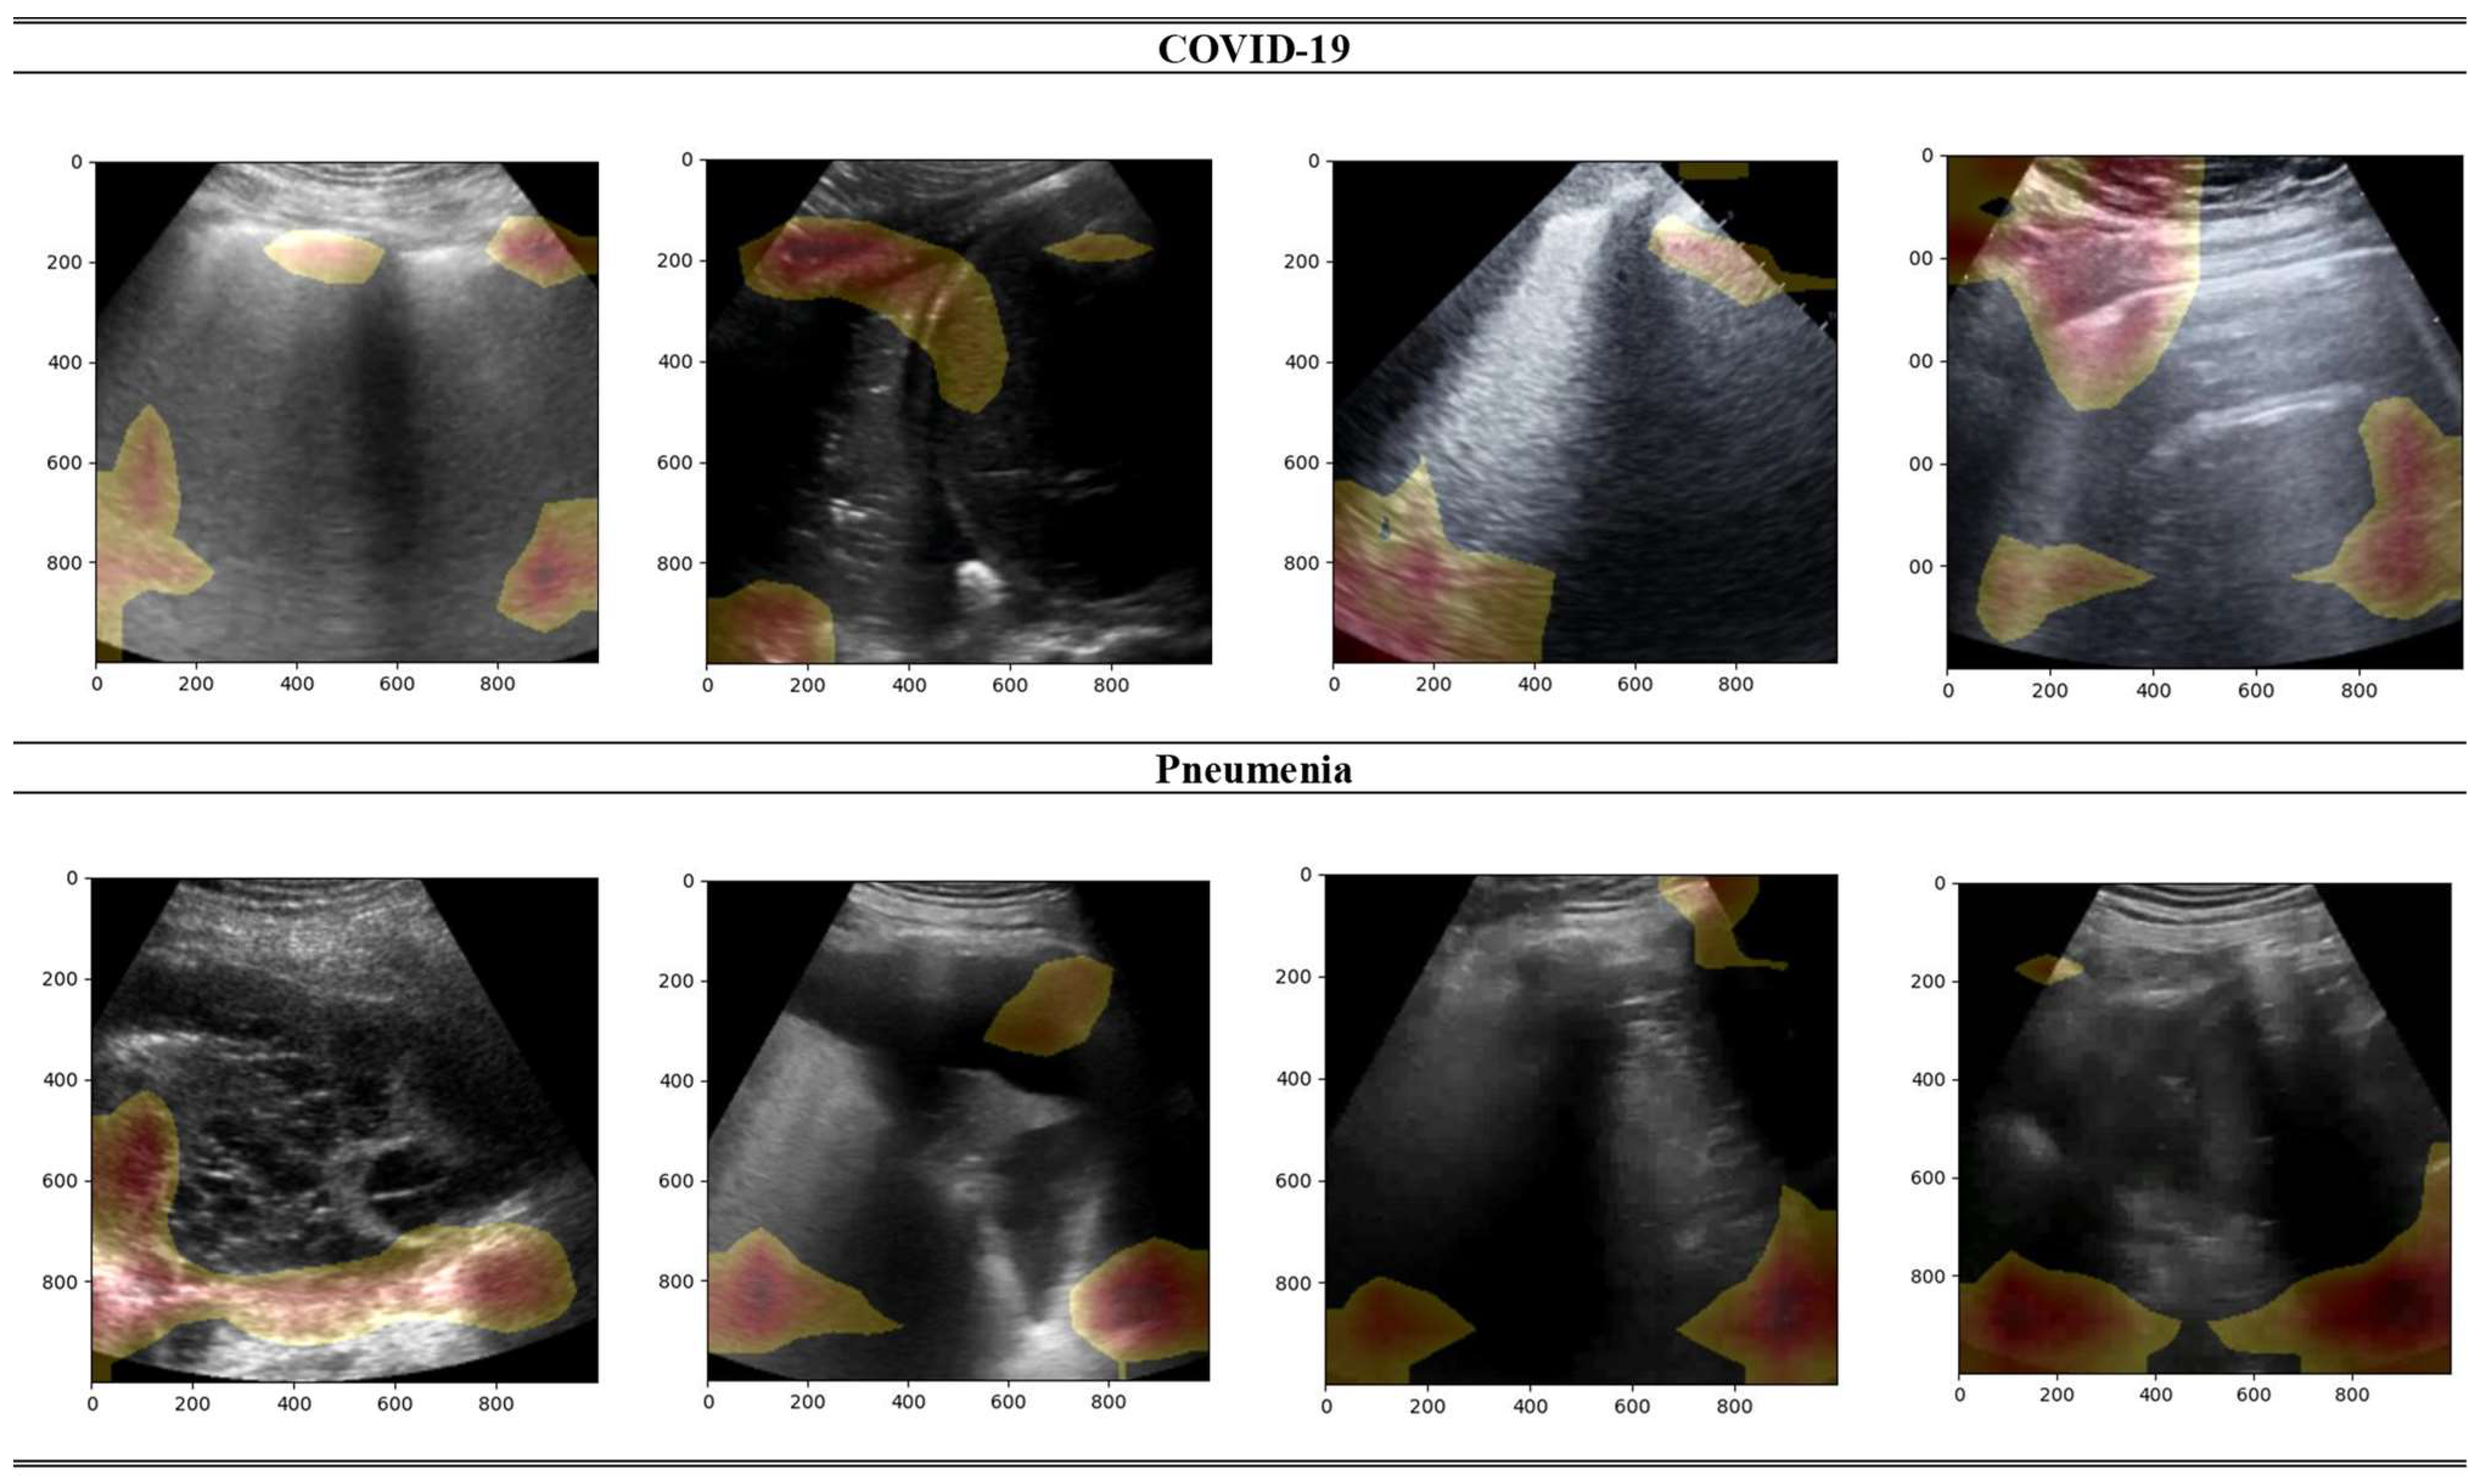

- Born, J.; Wiedemann, N.; Cossio, M.; Buhre, C.; Brändle, G.; Leidermann, K.; Goulet, J.; Aujayeb, A.; Moor, M.; Rieck, B.; et al. Accelerating detection of lung pathologies with explainable ultrasound image analysis. Appl. Sci. 2021, 11, 672. [Google Scholar] [CrossRef]

- Roy, S.; Menapace, W.; Oei, S.; Luijten, B.; Fini, E.; Saltori, C.; Huijben, I.; Chennakeshava, N.; Mento, F.; Sentelli, A.; et al. Deep Learning for Classification and Localization of COVID-19 Markers in Point-of-Care Lung Ultrasound. IEEE Trans. Med. Imaging 2020, 39, 2676–2687. [Google Scholar] [CrossRef]